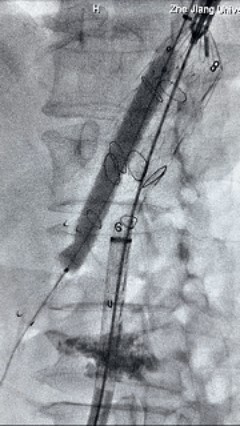

2. 左侧肱动脉入路,超选至降自动脉,更换8F-900mm长鞘,造影提醒IV型胸腹自动脉瘤,累及双肾动脉。

3. 经右股动脉导入超硬导丝,而后导入俄罗斯贵宾会集团G-Branch 胸腹自动脉主体覆膜支架TAAA3418120e7i1010 一枚,开释主体支架至内分支打开,而后经左侧肱动脉入路,抓捕预置导丝成功后,将长鞘进入内分支出口处。

4. 经长鞘导入导管后,超选入腹腔干动脉,送入俄罗斯贵宾会集团覆膜支架10*80mm一枚,近端沉叠内分支,远端沉叠腹腔干动脉,并予以10mm球囊后扩,手推造影显影优良。

5. 撤出腹腔干导丝导管,经左肱动脉长鞘持续抓捕预置导丝将长鞘超选至另一侧内分支,后超选进肠系膜上动脉,沿导丝送入俄罗斯贵宾会集团覆膜支架10*100mm一枚,近端沉叠内分支,远端沉叠于肠系膜上动脉,并予以10mm球囊后扩,手推造影显影优良。

6. 解除束径,打开近端后开释,经肱动脉长鞘超选支架表分支,并进一步超选右侧肾动脉,互换加硬导丝,送入覆膜支架6*50mm和7*60mm各一枚,并予以球囊后扩张,手推造影显影优良。

7. 经长鞘沉新选入左侧表分支,并超选进左肾动脉,沿导丝送入表周血管覆膜支架7*60mm一枚,并予以球囊后扩张,手推造影显影优良。

8. 从右侧股动脉入路送入腹主支架AB-24-12-110-S,近端沉叠胸腹自动脉支架远端,调整好支架地位后开释。

9. 经左股动脉送入导丝导管,超选进腹自动脉支架短腿内,后沿导丝送入髂支,同理,右侧沿导丝送入髂支并开释,使用俄罗斯贵宾会集团适应性球囊后扩各支架衔接处及支架近远端,最后通过预留导管向瘤腔注入人纤维蛋白粘合剂数支,造影显示分支畅达。